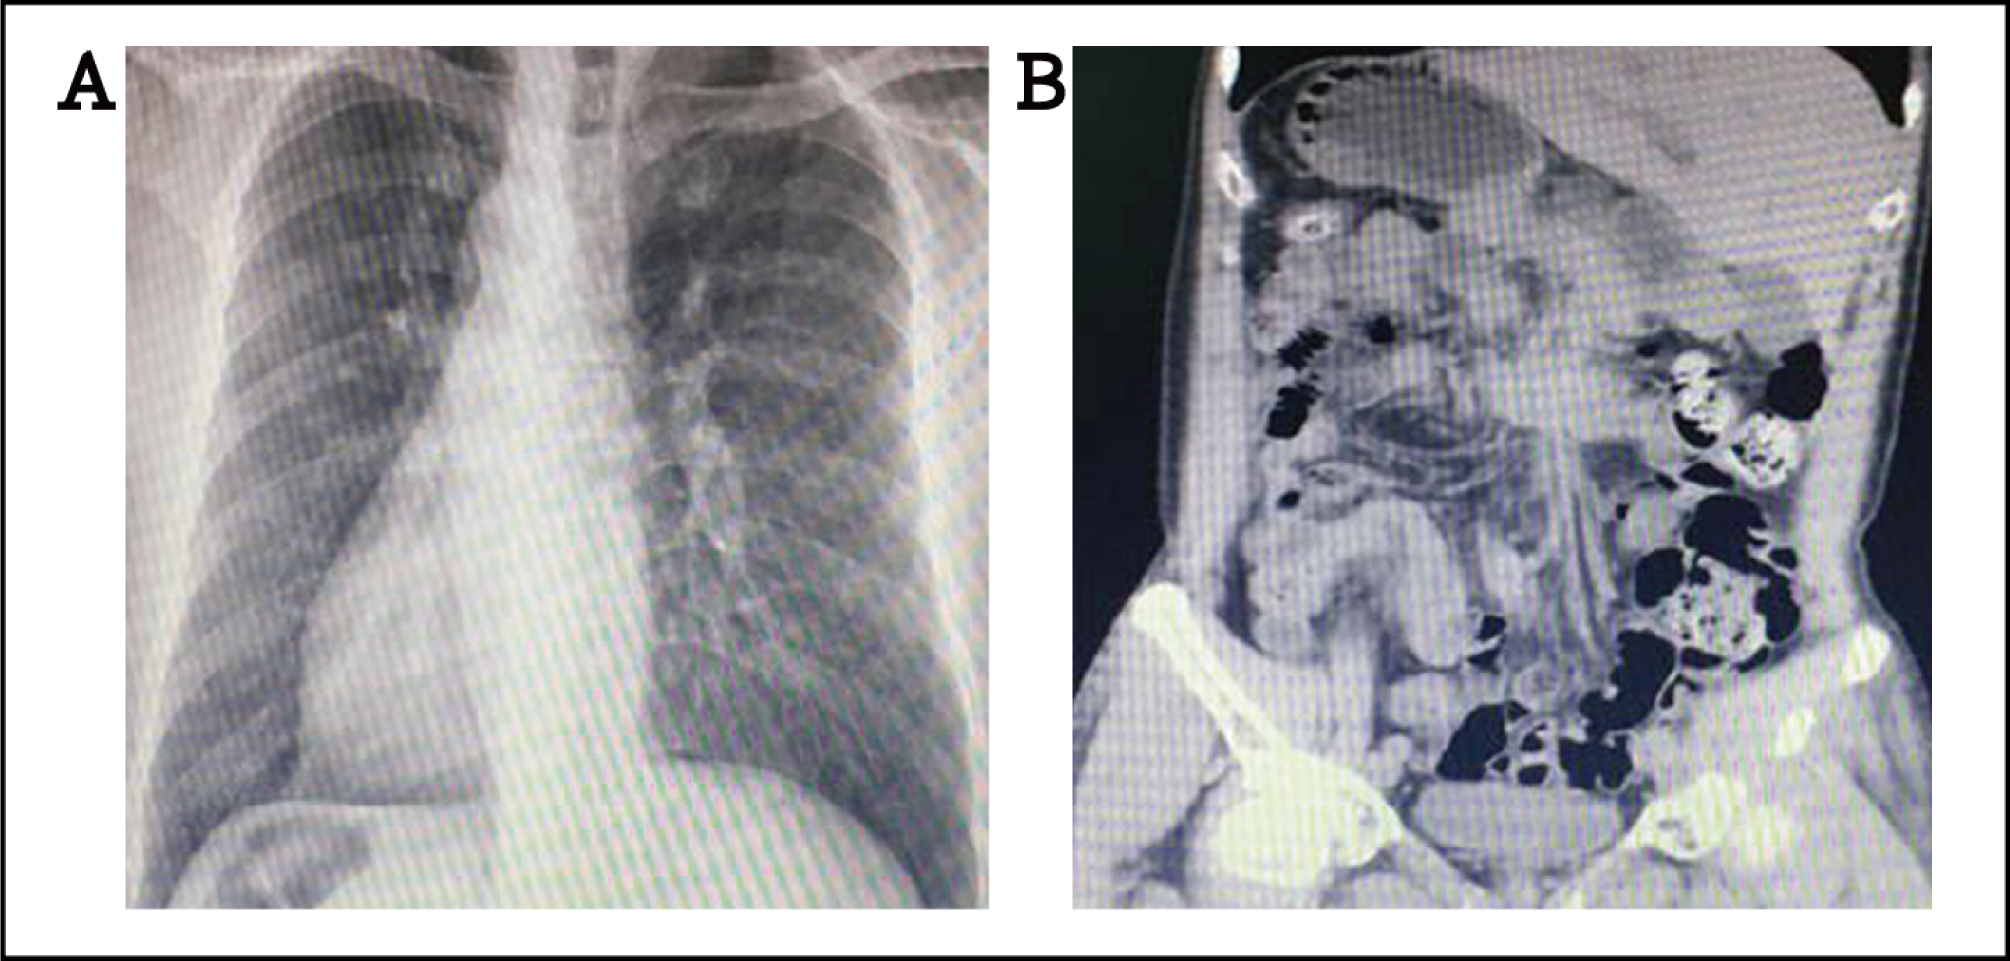

A 56-year-old hypertensive and dyslipidemia male patient with known dextrocardia (complete situs inversus type) diagnosed with coronary artery disease (CAD) four years ago, was admitted to our hospital due to aggravated symptoms of physical activity-related chest tightness and shortness of breath. The chest X-ray showed dextrocardia with a rightsided stomach air bubble. Apex located right chest, aortic arch and descending aorta were also on the right (Fig. 1A). Coronal computed tomography (CT) scan showed complete situs inversus (Fig. 1B). Moreover, the patient was diagnosed with coronary artery disease and underwent coronary angiography (CAG) four years ago, which found 50% diameter stenosis of the right coronary artery (RCA).

(A) Chest X-ray showing dextrocardia with a right aortic arch, right-sided stomach air bubble; (B) coronal CT scan showing the complete situs inversus. CT: computed tomography.